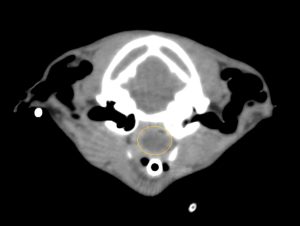

こんにちは。獣医師の永井です。 今回は肺葉捻転についてです。 犬猫の肺はバナナの房のように前葉、中葉、後葉(副…]]>

こんにちは。獣医師の永井です。 今回は肺葉捻転についてです。 犬猫の肺はバナナの房のように前葉、中葉、後葉(副…]]>